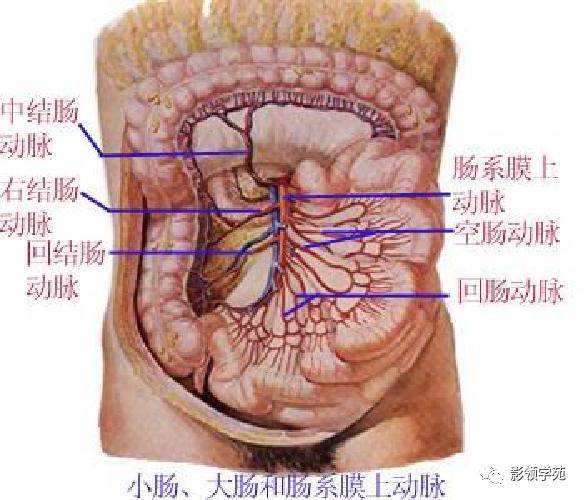

腹部动静脉

腹部动静脉